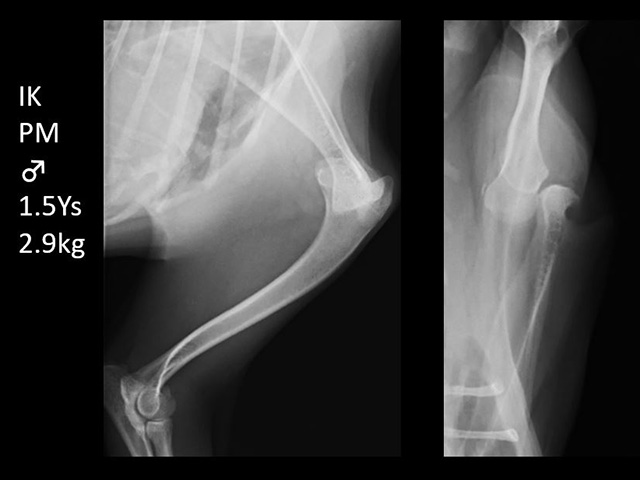

膝蓋骨脱臼Patellar Luxation

トイプードルなどのトイ種と呼ばれる小型犬に多い膝蓋骨(膝のお皿)脱臼は、後に関節軟骨の磨耗に伴う変形性膝関節症や前十字靭帯断裂を引き起こす可能性の高い厄介な運動器病です